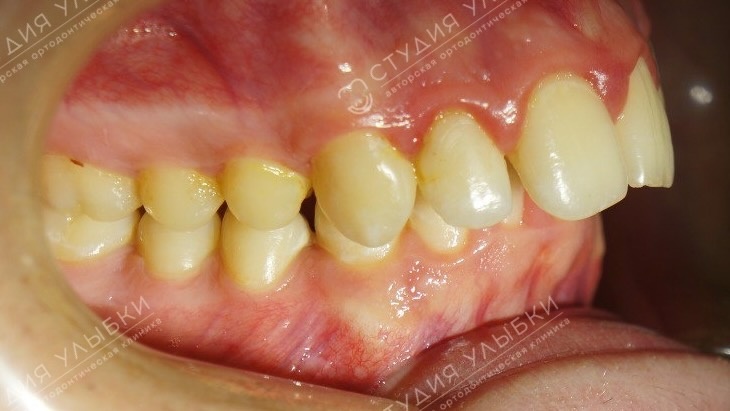

Фотопротокол — стандартные фотографии лица и зубов

Фотопротокол — обязательная часть диагностики перед брекетами у взрослых пациентов.

Для оценки линии улыбки делают фотографии — они показывают, насколько зубные ряды заполняют линию улыбки, какая высота уровня десны по отношению к зубам. Также оцениваются профиль лица и асимметрия.

Что включает фотопротокол:

• Лицо анфас и в профиль

• Улыбка в покое и при улыбке

• Положение зубов при смыкании

• Вид зубных рядов изнутри

Зачем нужен фотопротокол:

• Фиксация исходного состояния

• Контроль динамики лечения

• Выявление асимметрий и эстетических нюансов